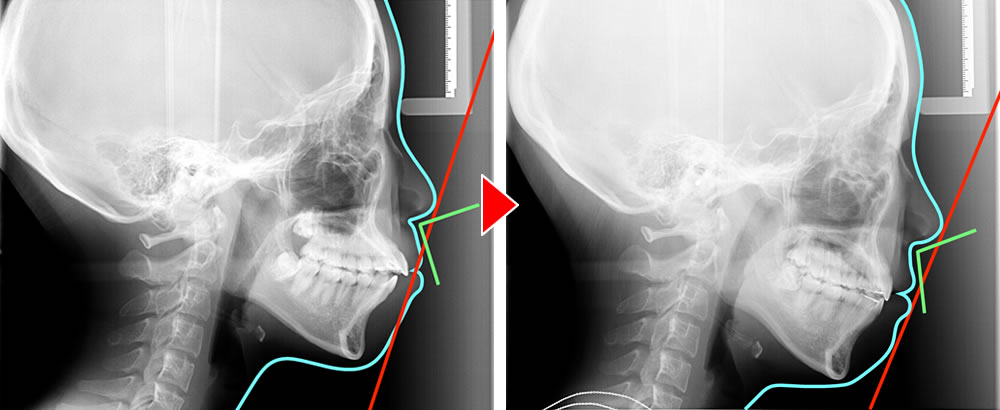

上下顎の前歯の傾斜も唇側傾斜しているため、しっかりと歯軸の改善をしつつ、噛み合わせを治す必要があるため、上下顎小臼歯を抜歯する診断をしました。矯正前・矯正後の横顔のレントゲンからも、口元の突出感、ナゾラビアルアングル(鼻と上唇がなす角度(鼻唇角)のこと。この角度は横顔の美しさの基準の一つで、一般的に90~110度が理想的とされています)の改善、上下顎前歯部の歯軸の改善が確認できました。